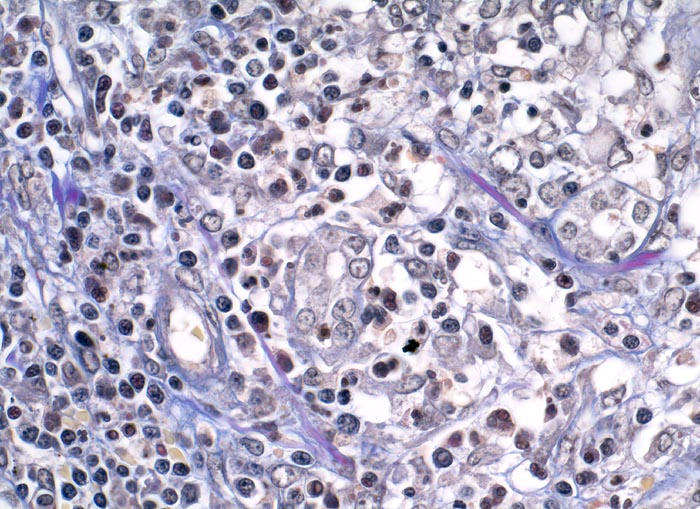

PathoPic ID 5003 - extrakapilläre Glomerulonephritis bei Morbus Wegener

extrakapilläre Glomerulonephritis bei Morbus Wegener

Systemerkrankung/Immunpathologie

Niere

Niere, Harnwege

Lymphohistiozytäre und teils granulozytäre Entzündung im tubulointerstitiellen Raum.

Rapid progressive Glomerulonephritis mit Entwicklung einer Oligurie innert weniger Tage. Fieber und Nachtschweiss. Chronische Sinusitis. cANCA erhöht.

Histologie

400